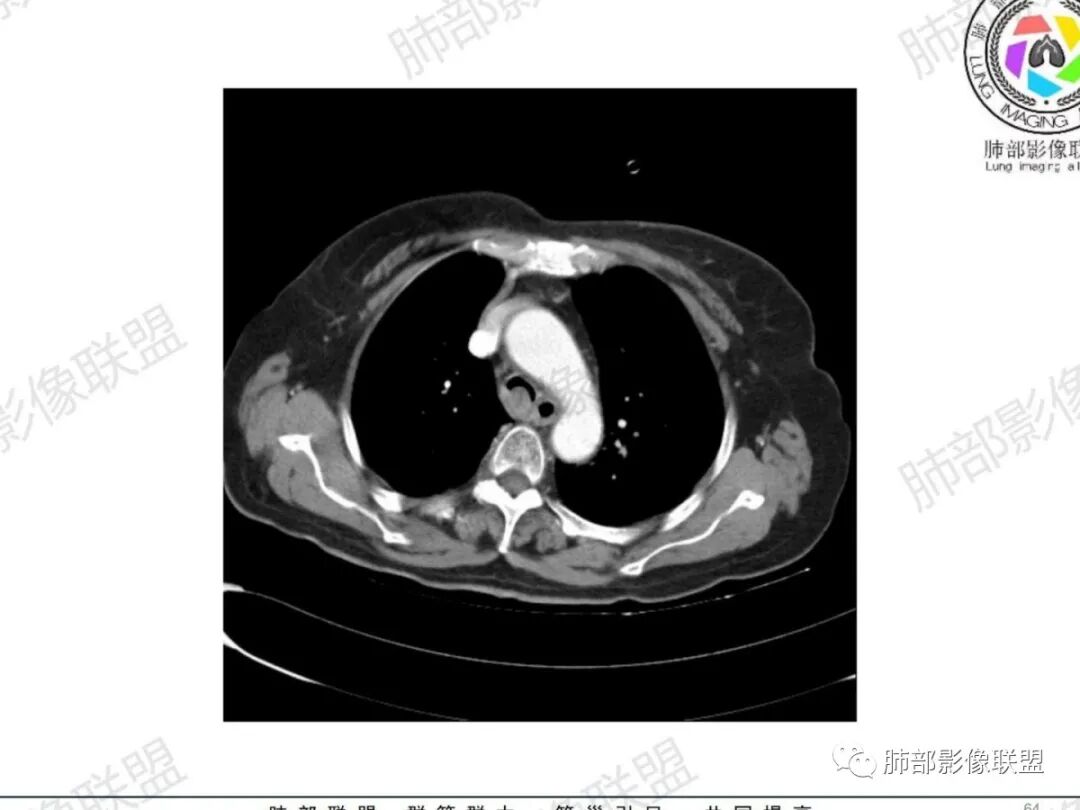

主支气管后缘外可见一实性结节,病变跨支气管管壁生长,部分突向管腔内,病变边缘光滑,平扫密度均匀,增强后尚均匀强化,纵隔淋巴结肿大不明显。

气管右后侧壁结节,结节向气管腔内突出,气管壁增厚,轻度强化,左侧甲状腺占位,考虑气管原发肿瘤,腺样囊性癌?类癌?

老年人,气管后壁结节,部分突腔外,考虑恶性,腺样囊性癌可能大,鉴别炎性肌纤维母细胞瘤

女,69反复咳嗽1年,胸闷二天,气管腔内见结节影,病灶突向腔内,管腔狭窄受压呈月牙状改变,增强扫描轻度强化,考虑腺癌?左侧甲状腺病变,不除外转移性病变。

气管结节,不均匀明显强化,跨气管壁,老年女性,考虑恶性——原发:腺样囊性癌、鳞癌、类癌;转移:甲状腺癌?转移。强化部分与甲状腺基本一致,转移瘤可能性大。

无蒂,无颈,气管侧后壁(特殊部位),虽然是老年女性年龄不符合,但是腺样囊性癌仍做首要考虑,还要考虑鳞癌。

主支气管腔内外见软组织肿块,密度不均,不均匀强化,腔内肿块边缘光滑,增强可见不均匀强化,病程长,考虑良性肿瘤性病变,支气管平滑肌瘤?甲状腺左侧叶结节,考虑甲状腺腺瘤或结节性甲状腺肿。

老年女性,慢性病程,反复咳嗽,胸闷2天,支气管内见新生物突向管腔,增强轻中度强化,无明显坏死,左侧甲状腺内见低密度结节,增强示低密度灶内结节状明显强化结节,肺部多发结节,考虑转移,鉴别粘液表皮样癌,腺样囊性癌

气管右后壁占位,平扫密度稍低于肌肉

增强后与肌肉类似,部分强于肌肉,提示强化

内外边缘光滑

宽基底与气管相连

附近壁增厚

前方见一小淋巴结,后内侧与食道联系很紧

宽基底,腔内外,看似边界清楚、光滑, 但是附近气管壁增厚,还是首先要考虑恶性,附近淋巴结也不太放心,因为强化明显

病理类型:甲状腺如果是恶性的,还是要警惕转移瘤;原发的:倾向于恶性,老年女性,表面光滑, 鳞癌几率比较低;腺样囊性癌确实要考虑

结果:腺样囊腺癌